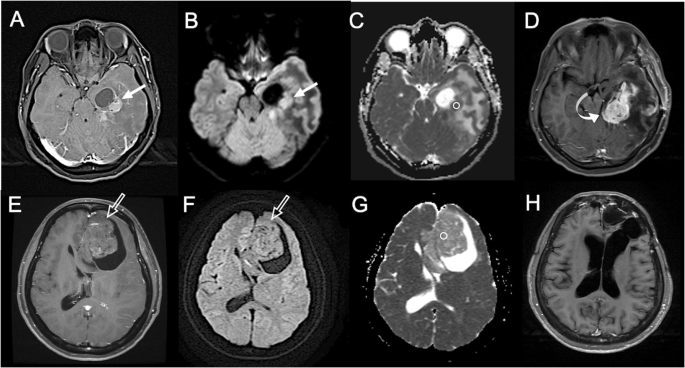

结果解读:新兴技术能早期检测治疗反应:例如DWI在脑胶质瘤中,低ADC值提示高细胞密度、预后差(图9,ADC=0.72×10⁻³mm²/sec的肿瘤3个月复发,而ADC=1.42×10⁻³mm²/sec的肿瘤72个月无复发);PET在霍奇金淋巴瘤中,SUV降低50%提示治疗有效(图11,预处理SUV=3.0,治疗后SUV=1.5,RECIST误判为无反应但PET提示有效)。

特异性与敏感性:例如在脑胶质瘤中,ADC值的敏感性为85%(能区分高/低级别胶质瘤),特异性为78%(图9);在淋巴瘤中,SUVmax的敏感性为90%(治疗后降低≥50%提示有效,图11)。

- 脑胶质瘤中,低ADC值(≤1.0×10⁻³mm²/sec)患者的中位生存期为12个月,显著短于高ADC值患者(24个月,P<0.01,图9);